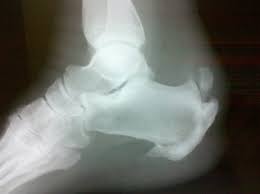

- Ανάπτυξη οστεόφυτου στο πίσω μέρος της πτέρνας (Καταφυτική τενοντίτιδα)

Ανάπτυξη οστεόφυτου στο πίσω μέρος της πτέρνας (Καταφυτική τενοντίτιδα)